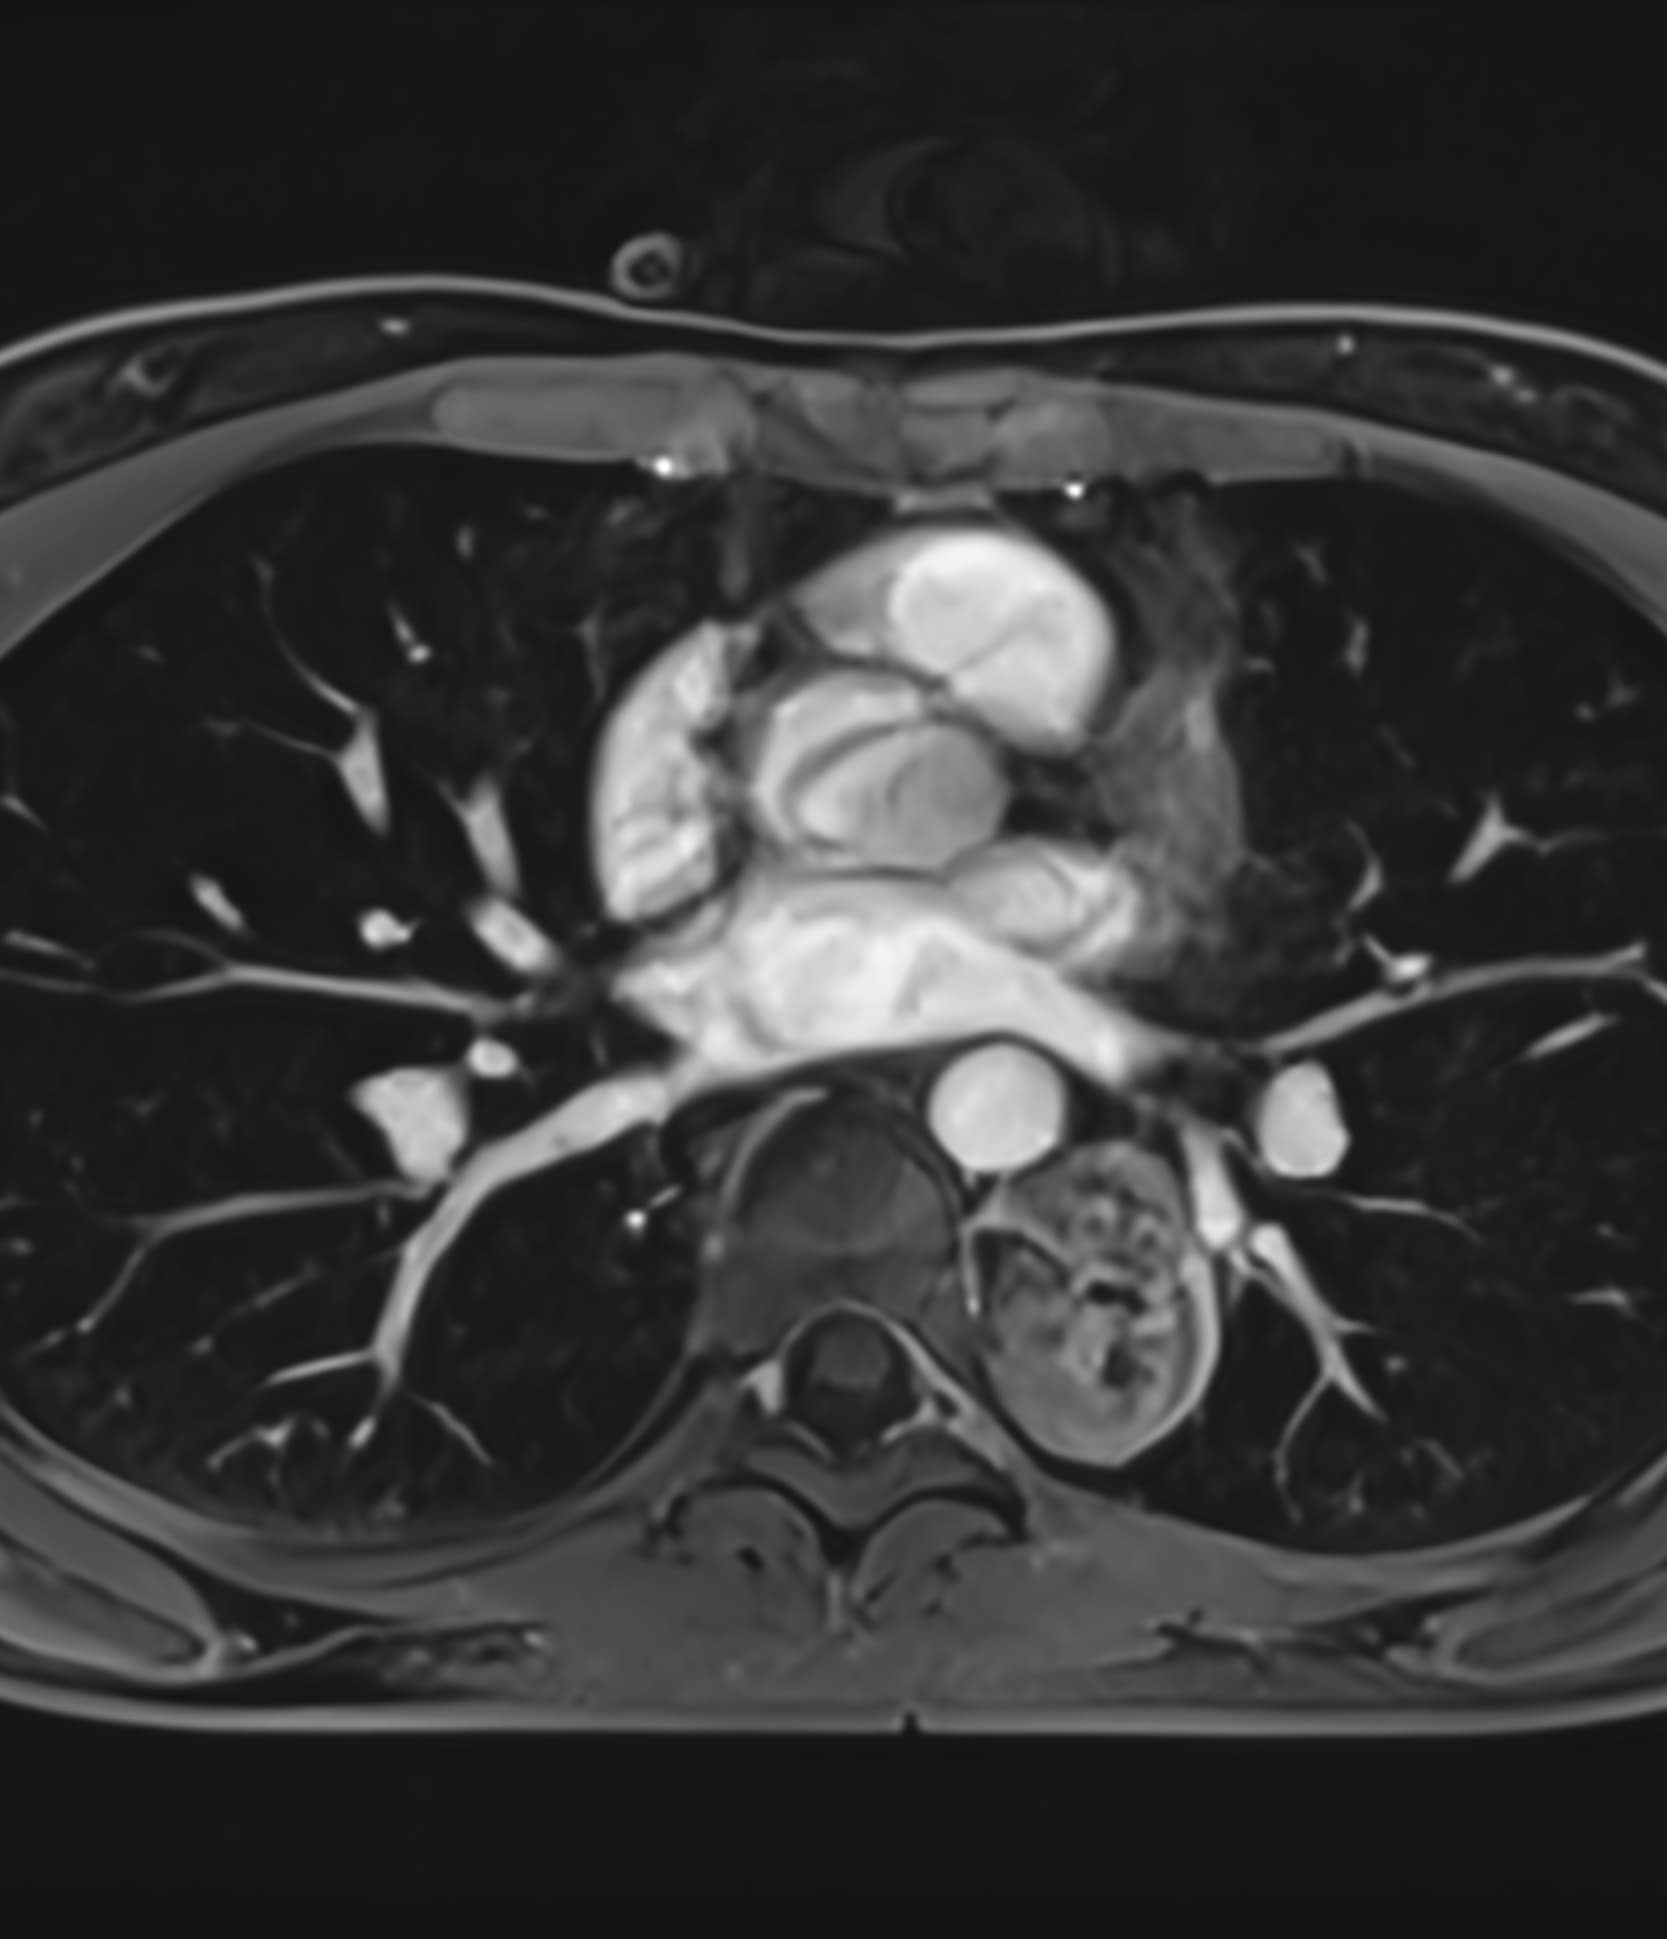

Δείτε πραγματικά παραδείγματα του SwiftMR™ σε διάφορα συστήματα MRI και ανατομικές περιοχές

Scan time 03:08

Scan time 1:12